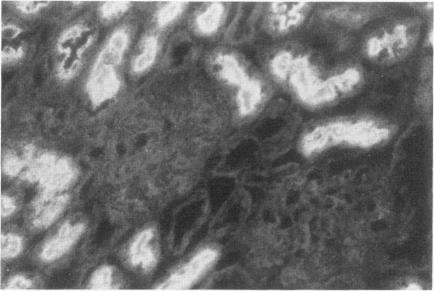

To investigate the role of glomerular epithelial cell (GEC) membrane proteins in the in situ formation of subepithelial immune deposits, the authors raised a rabbit antiserum against GEC that had been grown in culture (anti-GEC). By indirect immunofluorescence (IF) on normal rat kidney, anti-GEC stained proximal tubular brush border (BB). After intravenous injection into animals, granular glomerular capillary wall staining for IgG was present by IE and subepithelial immune deposits were identified by standard transmission and immunoelectron microscopy. Using the latter technique, injected anti-GEC IgG was identified beneath slit diaphragms and in endocytic-coated pits and intracellular vesicles of podocytes. Anti-GEC immunoprecipitated gp330 and two other proteins from radiolabeled BB. These proteins also were identified by sheep anti-rat Fx1A, the antiserum responsible for passive Heymann nephritis. Anti-GEC and anti-Fx1A also immunoprecipitated five identical proteins from surface-labeled GEC. Biosynthetically-labeled but not surface-labeled GEC contained immunoprecipitable gp330. Thus, injection into rats of antibodies raised against cultured GEC can produce subepithelial immune deposits, a disease process classically induced by antibodies to BB or its purified components. In addition to gp330, GEC and BB share other antigenic determinants that may contribute to the formation of these immune deposits.

为了研究肾小球上皮细胞(GEC)膜蛋白在原位形成上皮下免疫沉积物中的作用,作者制备了一种针对培养的GEC的兔抗血清(抗GEC)。通过对正常大鼠肾脏进行间接免疫荧光(IF)检测,抗GEC可使近端肾小管刷状缘(BB)染色。将其静脉注射到动物体内后,免疫酶标法显示肾小球毛细血管壁有IgG颗粒状染色,标准透射电镜和免疫电镜鉴定出上皮下免疫沉积物。使用后一种技术,在足细胞的裂孔隔膜下方、内吞小泡和细胞内小泡中鉴定出注射的抗GEC IgG。抗GEC从放射性标记的BB中免疫沉淀出gp330和其他两种蛋白质。这些蛋白质也可被羊抗大鼠Fx1A(引发被动型海曼肾炎的抗血清)鉴定出来。抗GEC和抗Fx1A还从表面标记的GEC中免疫沉淀出五种相同的蛋白质。生物合成标记而非表面标记的GEC含有可免疫沉淀的gp330。因此,向大鼠注射针对培养的GEC产生的抗体可形成上皮下免疫沉积物(这是一种典型地由针对BB或其纯化成分的抗体诱导的疾病过程)。除了gp330外,GEC和BB还共享其他抗原决定簇,这可能有助于这些免疫沉积物的形成。